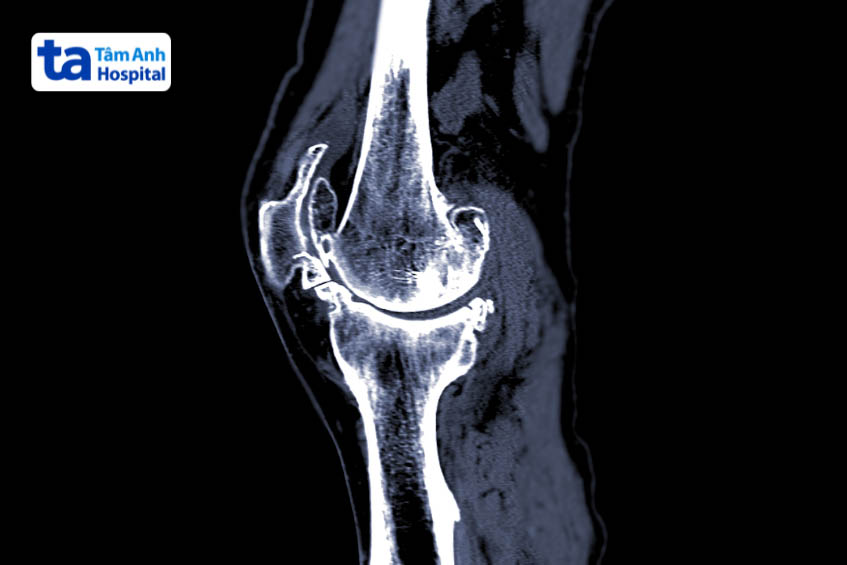

Ban đầu, bác sĩ sẽ tiến hành thăm khám lâm sàng, khai thác các thông tin cơ bản về tình trạng sức khỏe và các bất thường người bệnh đang gặp phải. Sau đó, bác sĩ có thể yêu cầu thực hiện một số phương pháp chẩn đoán cận lâm sàng như: